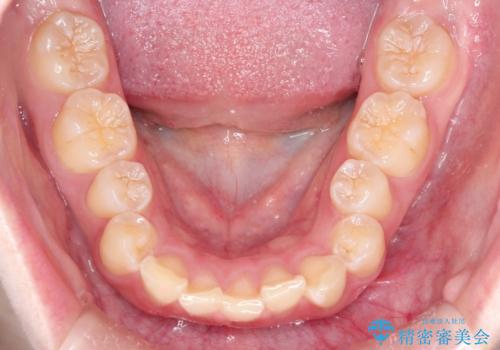

上顎の前歯の叢生があったのと、下あごの前歯が通常より1本欠損(先天欠損)していました。

上顎の歯と歯の間をわずかに削りスペースをつくり、並べる計画としました。インビザライン治療を選択されました。

しっかりとインビザラインを使用していただけたので、スムーズに治療を終了させることができました。